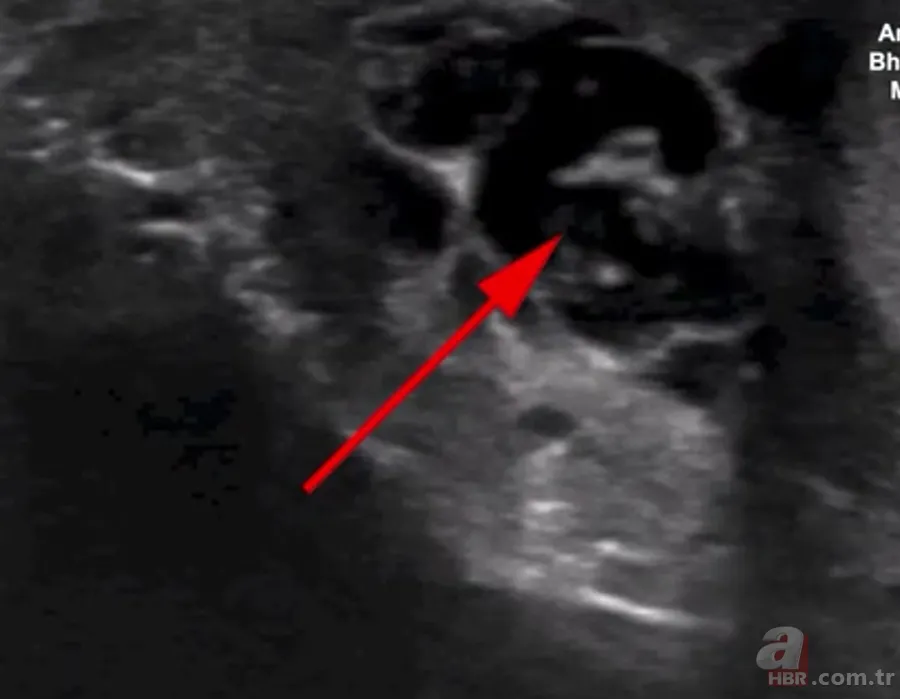

İngiliz Daily Mail gazetesinde yer alan habere göre, doktorlar hastanın skrotumunda hareket eden doğrusal yapılar keşfetti.